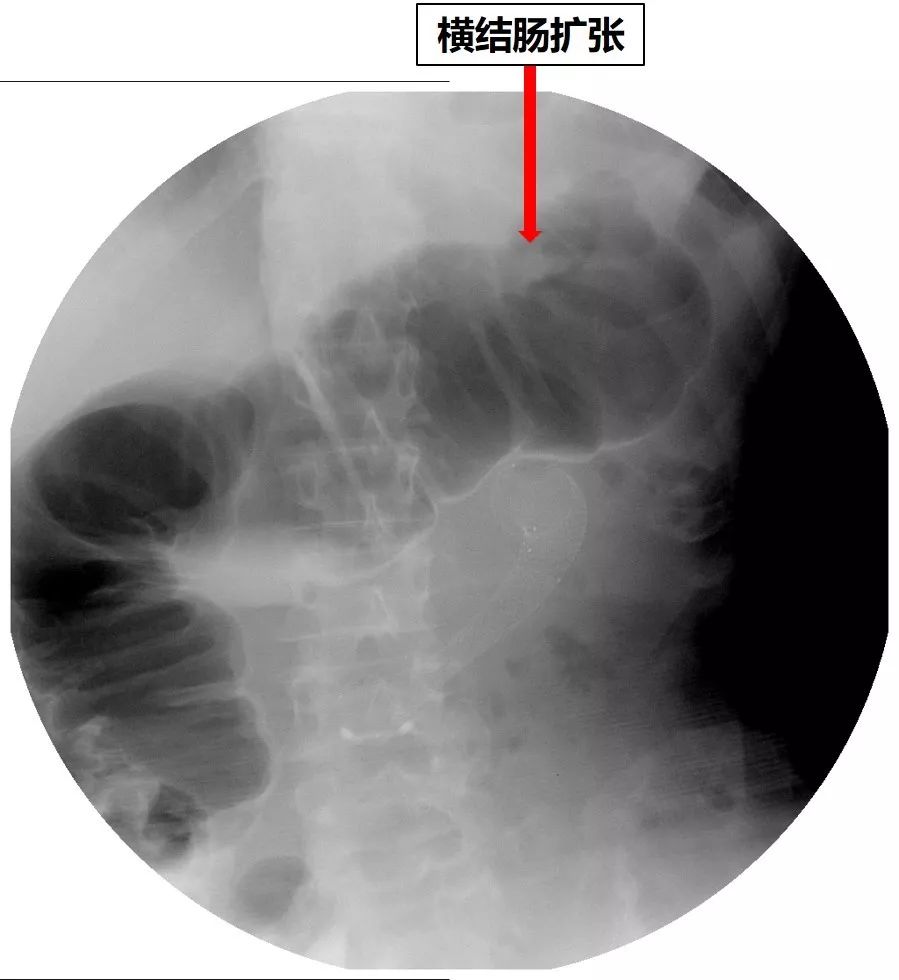

但是患者仍有恶心、呕吐症状,呕吐少量胃液。重新进行全消化道造影,又发现了新的问题:结肠脾曲梗阻!(图21、图22)

图21 X线平片见横结肠扩张

征得患者及家属同意后,于2019-1-10为患者放置结肠支架。术中结肠镜见结肠脾曲充血水肿,内镜无法通过。未见明确的肿物。结肠支架放置过程顺利,术后复查X线平片,见扩张的结肠回缩,造影剂通过了结肠脾曲(图23)。